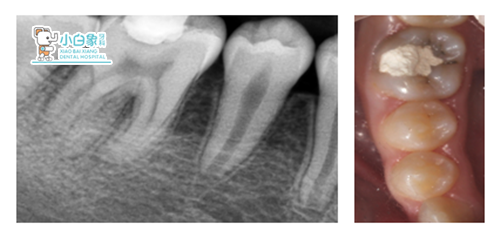

检查:颌面部查未见异常,口内查:46合面见白色充填物,叩(-),温度测试无反应。

X线:46远中牙周膜增宽,根尖见低密度影像

诊断: 46慢性根尖周炎16、26、36、37中龋27、47新生恒牙

治疗计划:46根管治疗+嵌体修复

治疗过程:1.46去除暂封,揭髓顶,拔髓,测近远中颊舌侧根长19mm,M3预备,荡洗根管,隔湿干燥,封木榴油一周复诊,试尖,牙胶尖+根管糊剂充填,树脂垫底,制作假壁,制备牙体,扫像,设计,研磨,试戴,上釉,粘结嵌体。